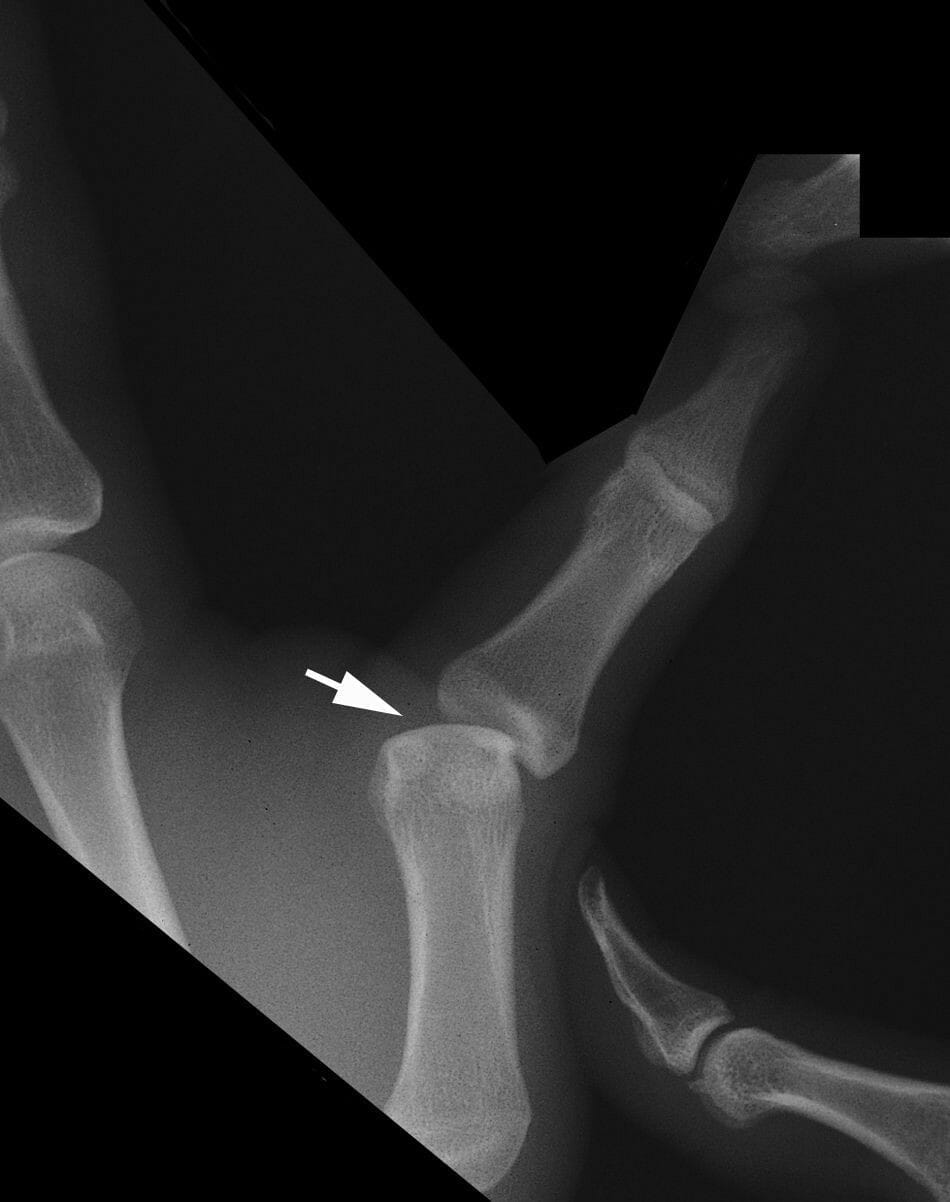

Unraveling the UCL Injury of the Thumb